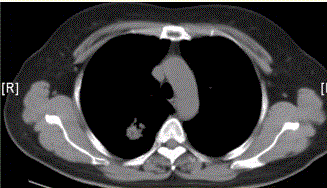

问题 患者女,54岁,无症状,常规体检透视时发现右上肺阴影。既往无结核病史。体格检查阴性。CT结果如下图。 该例最可能诊断为

选项 A.肺结核瘢痕 B.周围型肺癌 C.肺错构瘤 D.肺腺瘤 E.结核球 F.尘肺(硅沉着病)

答案 B

解析 B